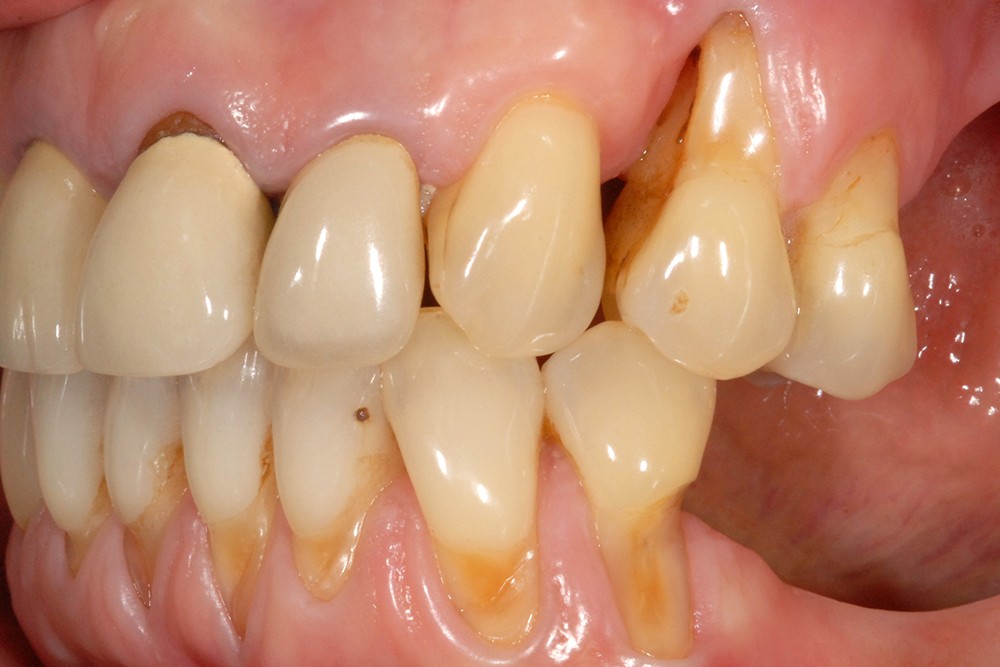

Lorsque l’abrasion est focalisée, en général au niveau cervico-vestibulaire, elle est essentiellement liée au brossage dentaire. Les particules abrasives contenues dans le dentifrice constituent le troisième corps qui s’interpose entre la brosse et les dents. Dans certains cas pathologiques favorisés par un environnement acide, la dentine radiculaire plus ou moins dénudée s’abrase fortement en cas de brossage iatrogène. D’importantes lésions cervicales non carieuses peuvent alors apparaître en peu de temps (fig. 3).

Lorsqu’une surface est soumise à de fortes pressions et qu’elle glisse le long d’une autre, des micro-cracks peuvent s’initier en subsurface puis se propager avec la répétition des cycles. Lorsque la propagation atteint la surface, des fragments de matériel assez important peuvent se détacher, ce qui se concrétise cliniquement par des lésions d’aspect cunéiforme, plus profondes que larges, encore appelées lésions d’abfraction (fig. 4). Bien que divers arguments cliniques et théoriques soient évoqués pour la justifier indirectement, la relation de causalité reste cependant spéculative. L’initiation et/ou l’élargissement de ces lésions seraient plutôt multifactoriels, liés à la combinaison des contraintes occlusales et du brossage dentaire, le tout dans un environnement acide.